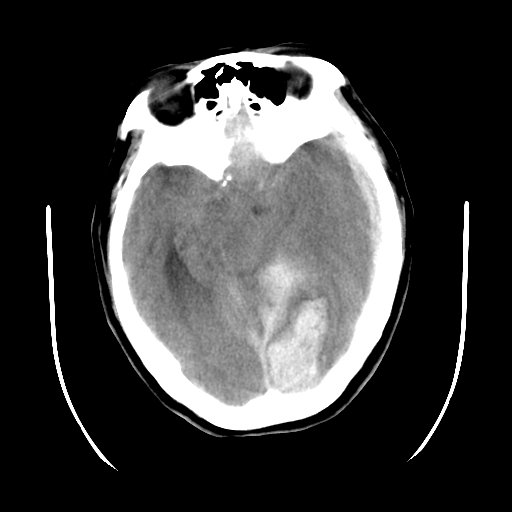

以下是引用gaoshengjiang在2007-10-7 9:18:00的发言:[br]左枕叶脑出血,左额颞顶部及纵裂硬膜下血肿,蛛网膜下腔出血,右颞叶脑梗塞。出血原因:患者年龄较大可能为动脉硬化或血管畸形?建议进一步临床检查。